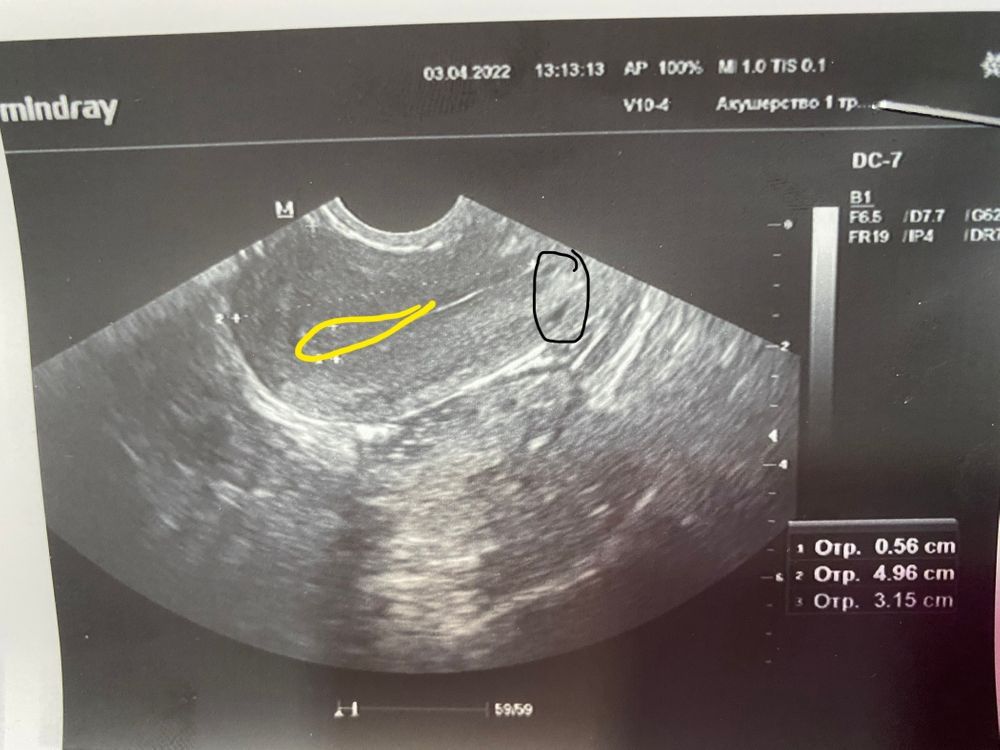

То что вы обвели это почти шейка и внешняя часть матки которая находится в брюшную полость. Там ПЯ ну ни как чисто физически быть не может. И скорее всего это очаг аденомиоза

А эндометрий это полоска посередине, там должно быть ПЯ. И какое ПЯ вы хотите увидеть при отрицательном хгч?

Вот тут при маточной беременности находится ПЯ

Нет. Это не пя) у вас матка сомкнута, вон узенькая полоска выше и левее точки. Она прям как полосочка такая немного изогнутая. Такая продолговатая как будто краешки белые и внутри темнее.

Эта точка обведённая даже не в полости матки по снимку. И пя не так выглядит) да и хгч у вас не Б